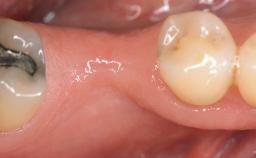

Connective-Tissue Graft to Increase the Width of the Keratinized Mucosa Around an Osseointegrated Implant

Adequate peri-implant soft-tissue thickness is essential not only for esthetic but also for functional reasons. In this case, Vincenzo Iorio Siciliano demonstrates how he achieved increased height and thickness of posterior peri-implant soft tissues to obtain a stable mucosal seal and a width of keratinized tissue favorable to toothbrushing.

The patient, a healthy 38-year-old woman, was referred for increasing the width of the keratinized tissues at the buccal aspect of dental implant 46. The site exhibited a premature-closure screw exposure caused by trauma during chewing, with inadequate keratinized tissue.